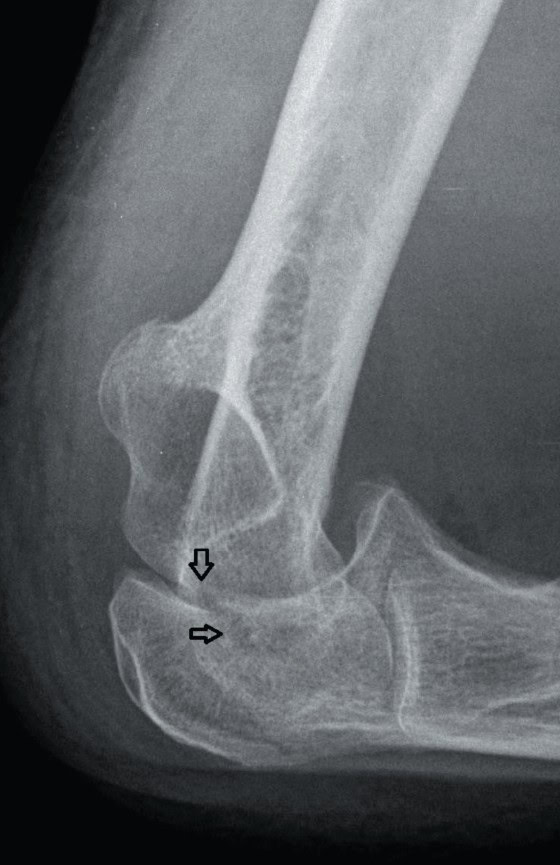

Diagnosis: The x-ray reveals a fracture of the olecranon. In a patient with dementia and this type of fracture, there may not be a history of a fall or trauma. A cast splint at 90 degrees at the elbow and follow up with an orthopedist are appropriate for this patient.